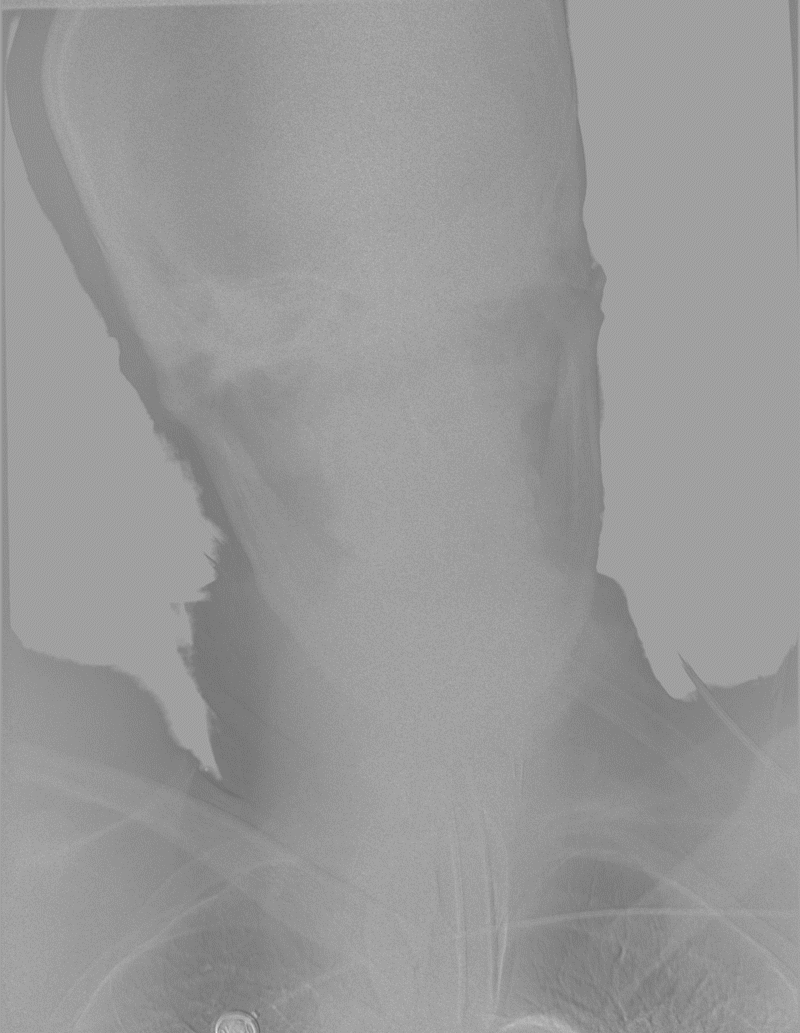

术前检查:

左右滑动切换图片

04 术后造影

术后检查: